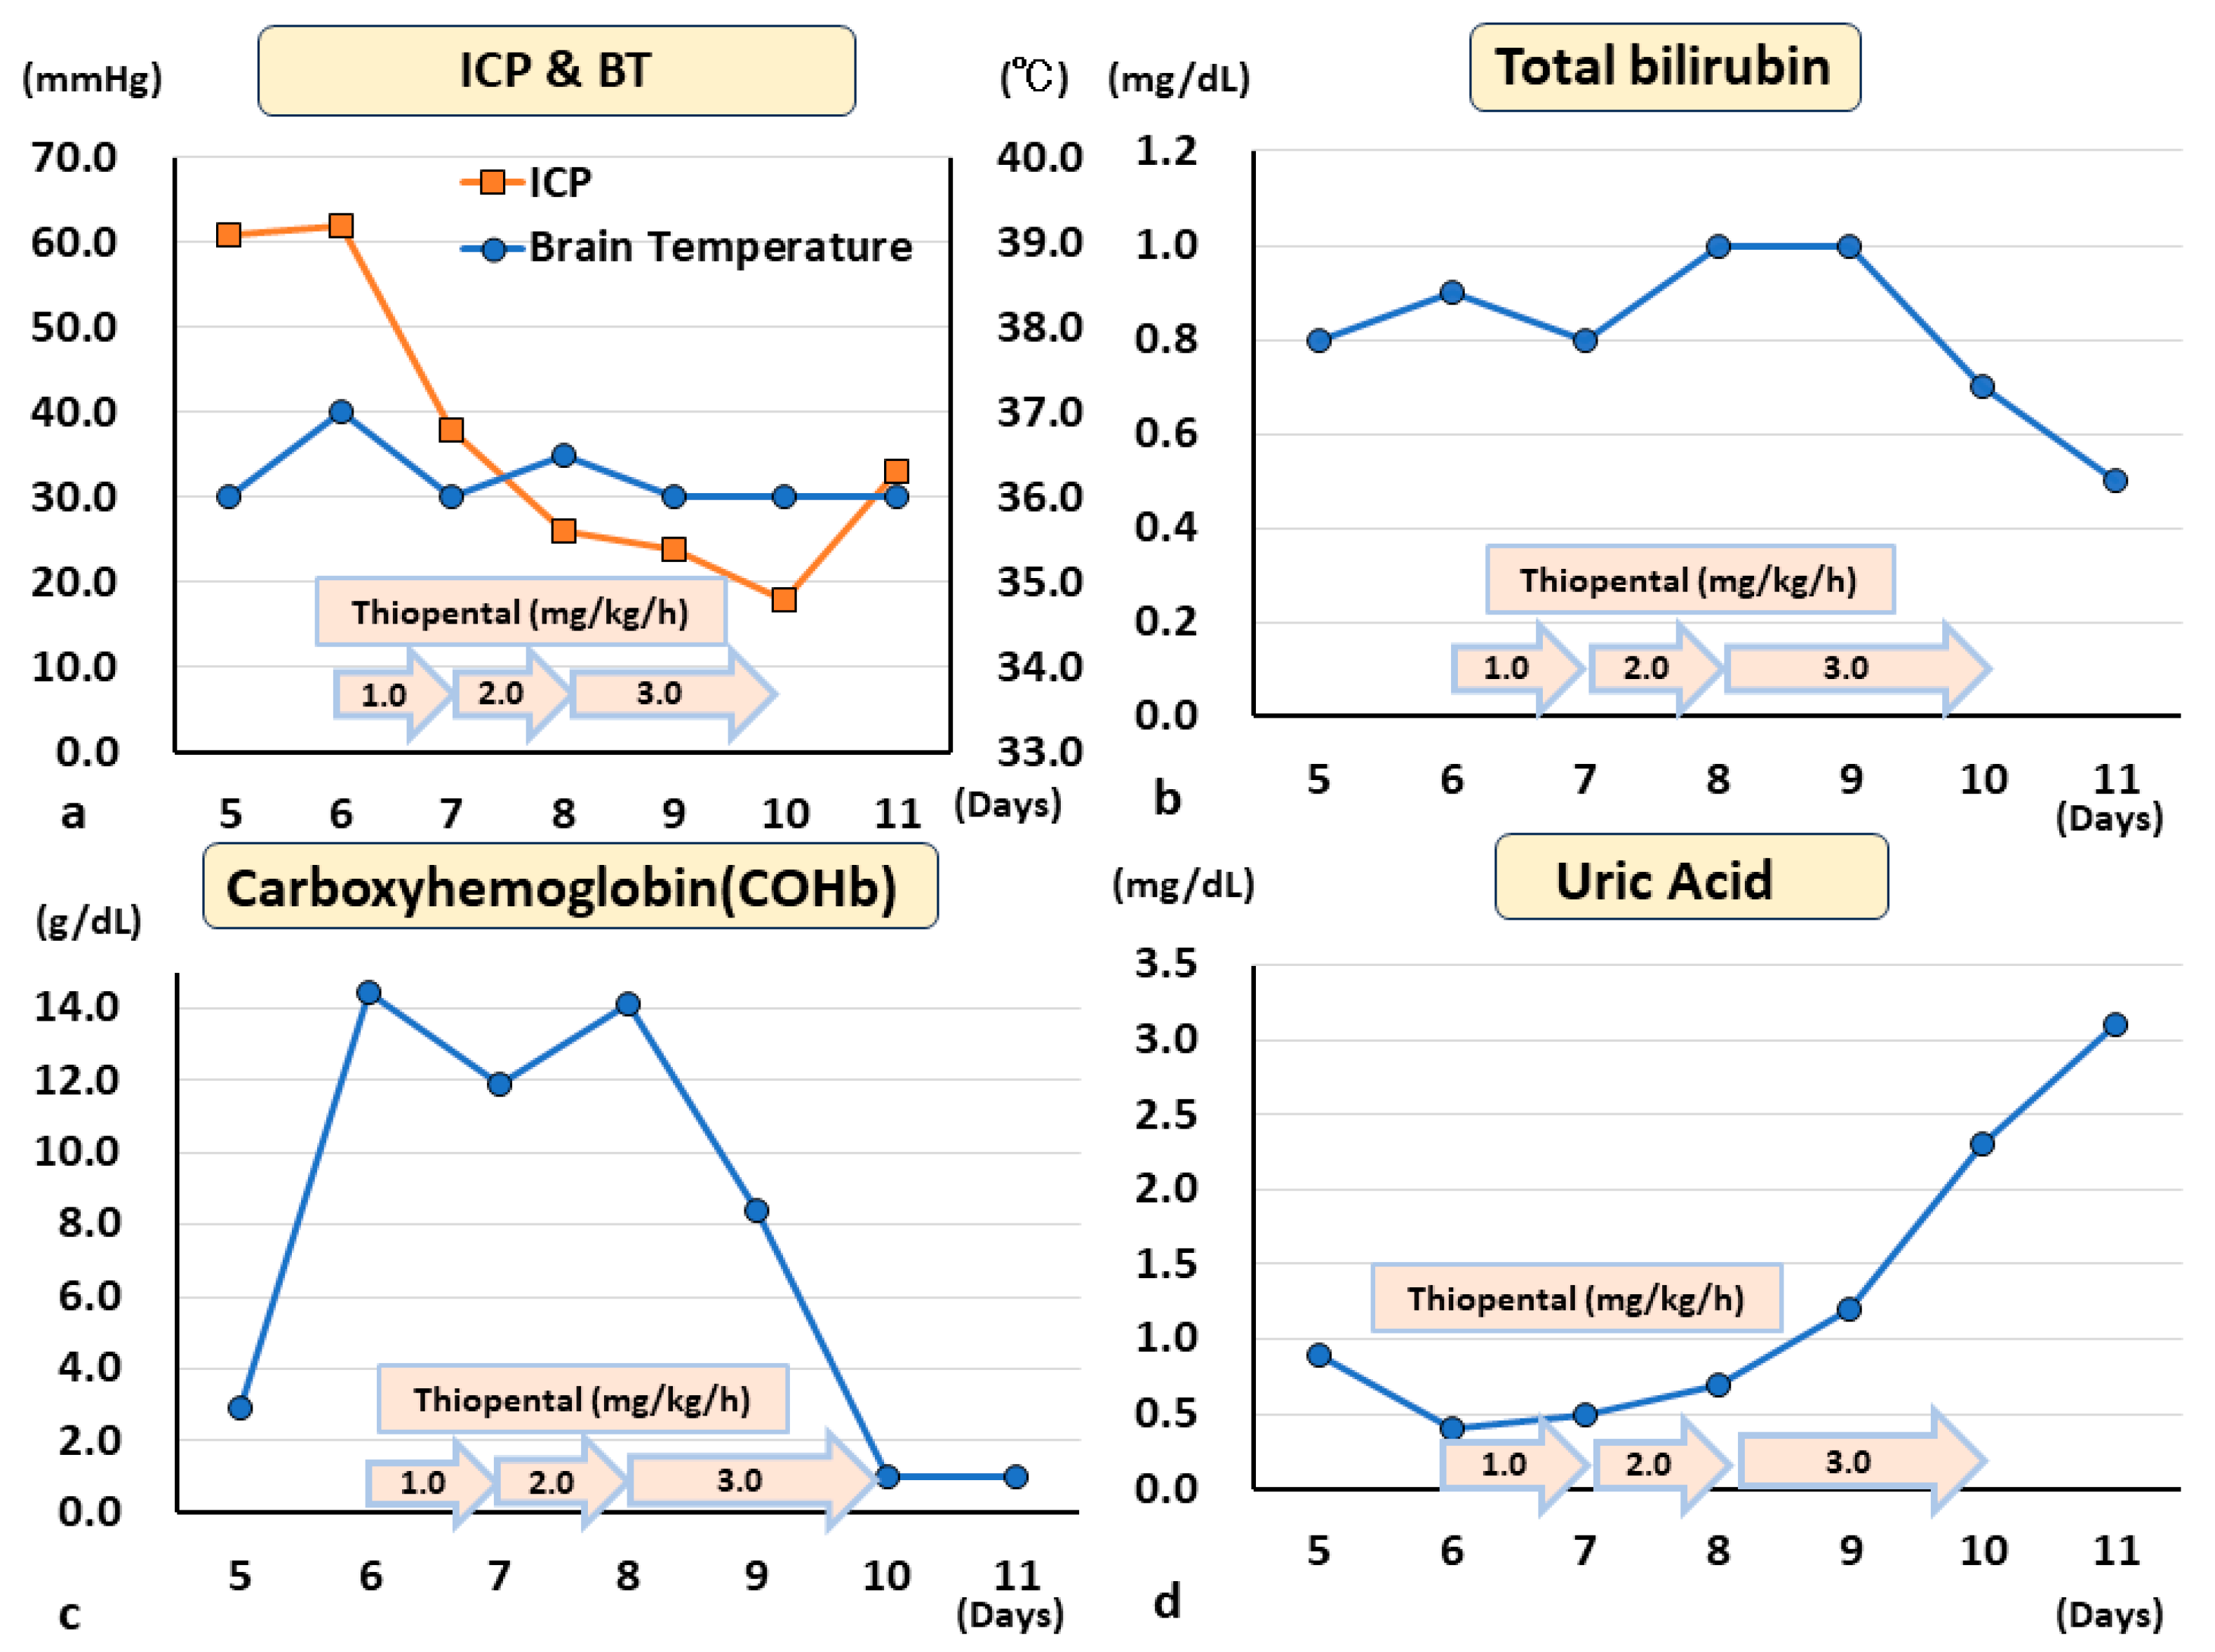

4. Clinical Case